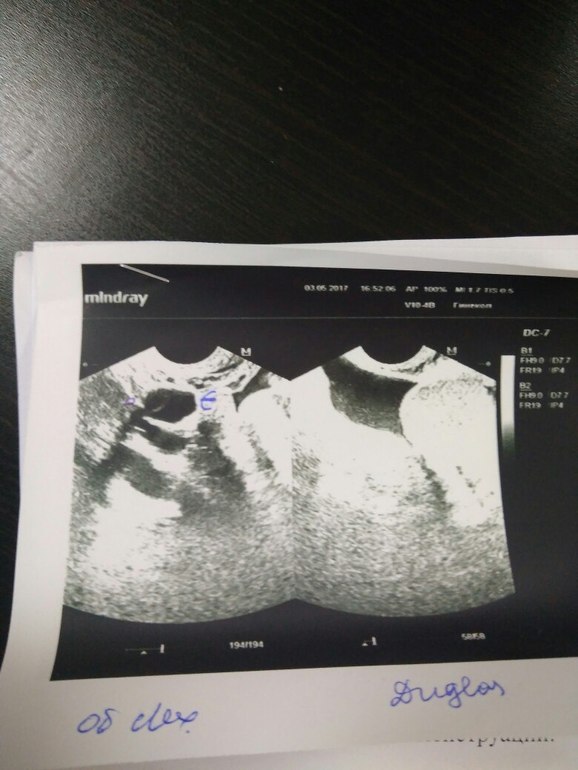

Маленькое ЖТ на 14ДЦ,когда была овуляция и была ли?

В правом яичнике ЖТ и всего 14мм!!! 5 дней назад фолликул был 12.5мм. Не пойму была ли овуляция?

И ести ЖТ 14мм, то оно не сможет нормально работать?

Фото не пойму чего!

ЖТ маленькое, потому что О была скорей всего пару дней назад и жидкости у вас в заднем своде много, ЖТ обычно смотрят на 7 дпо, не переживайте, все у вас нормально.